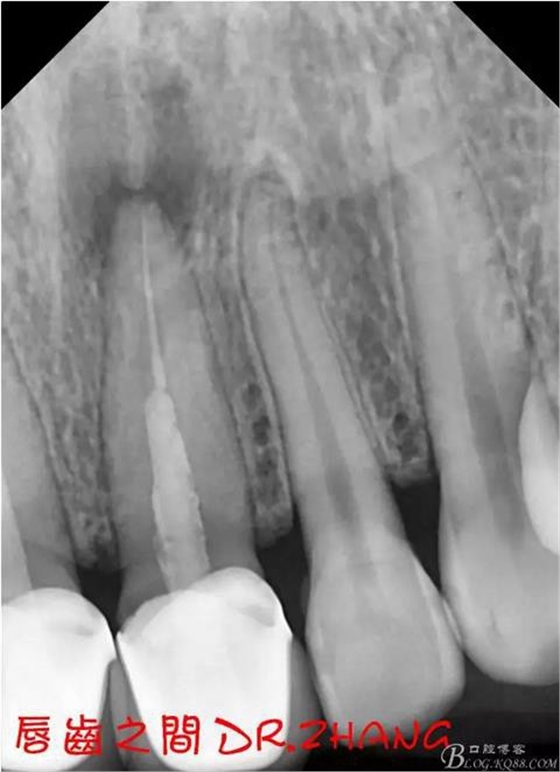

X片示11 21根管內(nèi)有高密度陰影 根尖低密度陰影

處理:21從修復(fù)體舌側(cè)打開(kāi)通路 髓腔內(nèi)疑似纖維樁 高速和低速手機(jī)聯(lián)合去除樁核 在處理的過(guò)程中不斷拍片確認(rèn)方向 去除樁核后拔髓針去除牙膠 只有一個(gè)標(biāo)尖 膿液大量滲出 雙氧水和鹽水交替沖洗后 滲出減少 開(kāi)放髓腔 隔日復(fù)診